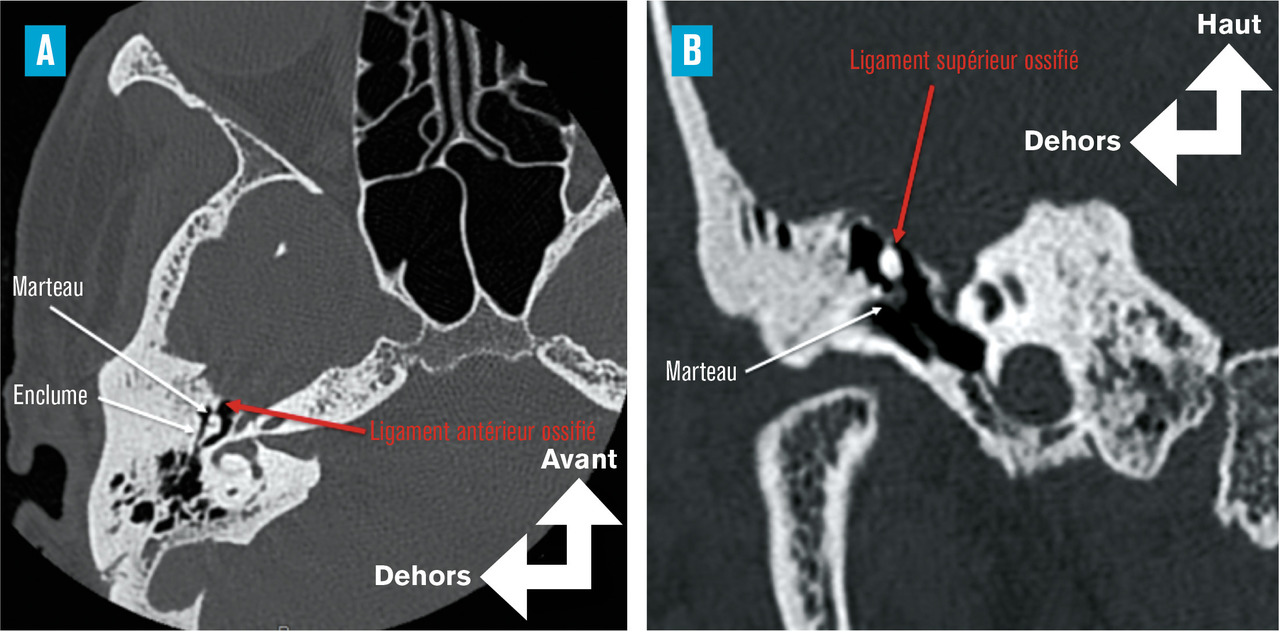

Le syndrome de House ou de Goodhill est responsable d’une surdité de transmission à tympan normal acquise, caractérisée par la fixation de la tête du marteau à son contenant osseux (la cavité de l’oreille moyenne) liée à l’ossification des ligaments antérieurs et/ou supérieurs du marteau (Pour mémoire, l’ostéogenèse imparfaite de Lobstein (« maladie des os de verre ») et la maladie de Paget peuvent être responsables d’une surdité de transmission à tympan normal du fait d’une atteinte d’un ou plusieurs osselets.